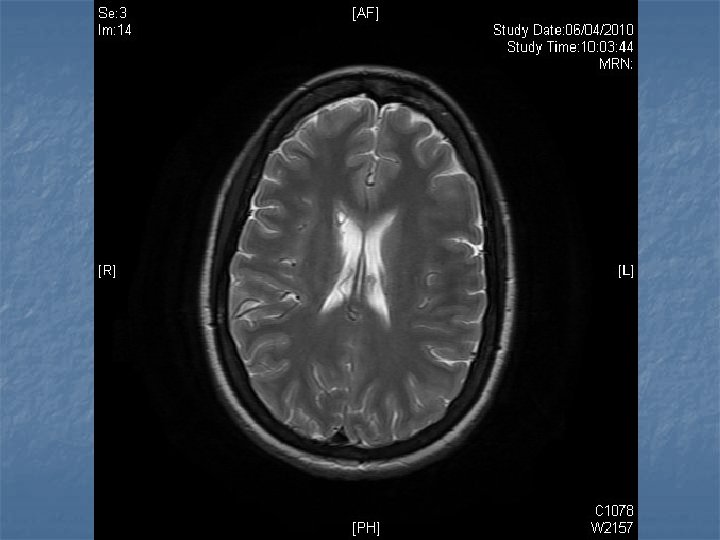

n n n PRETREATMENT INVESTIGATIONS: FBC, Renal and liver function, LDH, urate, Ig. GS. Histology review. Marrow aspirate+trephine (cytogenetics, immunology) CD 4 , HIV viral load. CT Scans. (MR Brain) (PET scan ) Echo / LVEF CMV, Hep B+C, Toxoplasma serology MAI screen. LP for CSF cytology +/- intrathecal Rx. (DLBC , Burkitt, Plasmablastic).

n n n PRIMARY CNS LYMPHOMA Typically occurs with marked immunosuppression CD 4<50. Marked reduction in incidence post HAART. Always EBV positive DLBC NHL. Commonly multifocal brain lesions. n High dose methotrexate iv Followed by brain XRT. n Poor prognosis survival months to 1 -2 years. n